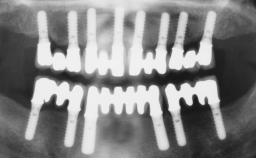

Conventional Loading of Six Implants in the Mandible and Final Restoration with a Full-Arch Metal-Ceramic FDP

# of Implants 6

Type of Implants One-Piece

Surgical SAC classification

SAC Level Advanced

Defining Characteristics Fully edentulous lower jaw to be rehabilitated with two or more implants

Modality > 4 implants, extending to mental nerve region

Bone Volume Horizontally and vertically sufficient